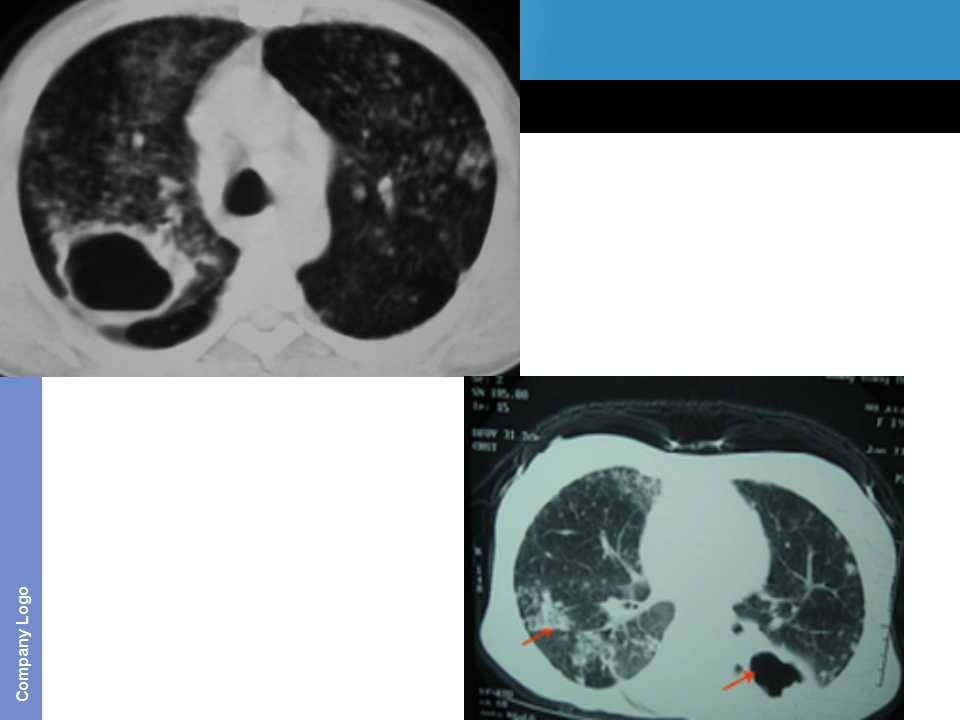

肺癌影像诊断